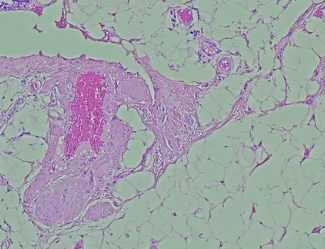

3. 진주색 구슬처럼 반짝이는 혹 – 기저세포암

- 피부암 중 가장 흔하지만 전이 위험은 낮은 기저세포암

- 보통 얼굴이나 목 등 자외선에 많이 노출된 부위에 발생

- 반투명하고 윤기 나는 혹처럼 보이며, 중심부가 살짝 움푹 파인 경우도 있음

- 표면에 실핏줄이 퍼지듯 보이는 특징

- 천천히 자라지만, 깊이 파고들며 주변 조직 침범 가능